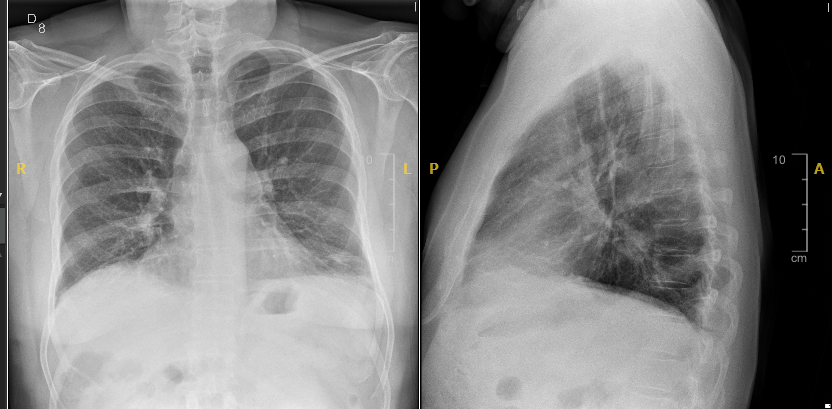

Eco Pulmonar: slidding pleural presentwe, lineas A, no aprecio lineas B ni derrame pleural.

Si bién la ecografía permite el diagnóstico y seguimiento de la TVP desde Medicina de Familia, en este caso con dorsalgia derecha, disnea y caída de la saturación de O2 en decúbito, se deriva a Hospital por sospecha de EP. La gasometría arterial no descarta la presencia de EP. Un AngioTAC confirmaría o no la EP, importante para el diagnóstico y seguimiento del paciente.